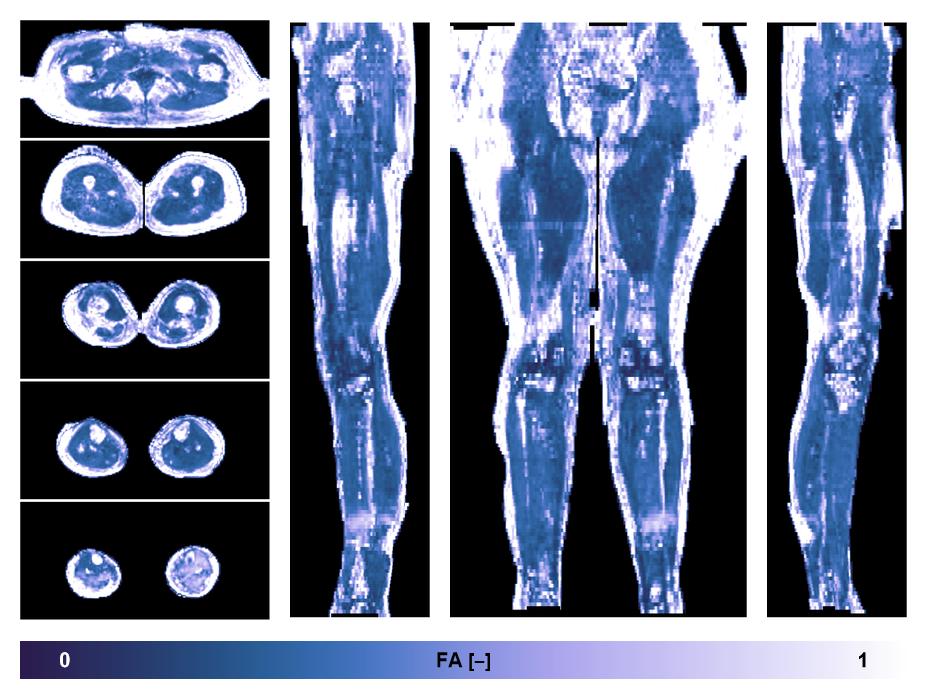

• Fractional anisotropy

IVIM corrected whole leg muscle fractional anisotropy obtained from diffusion tensor imaging.